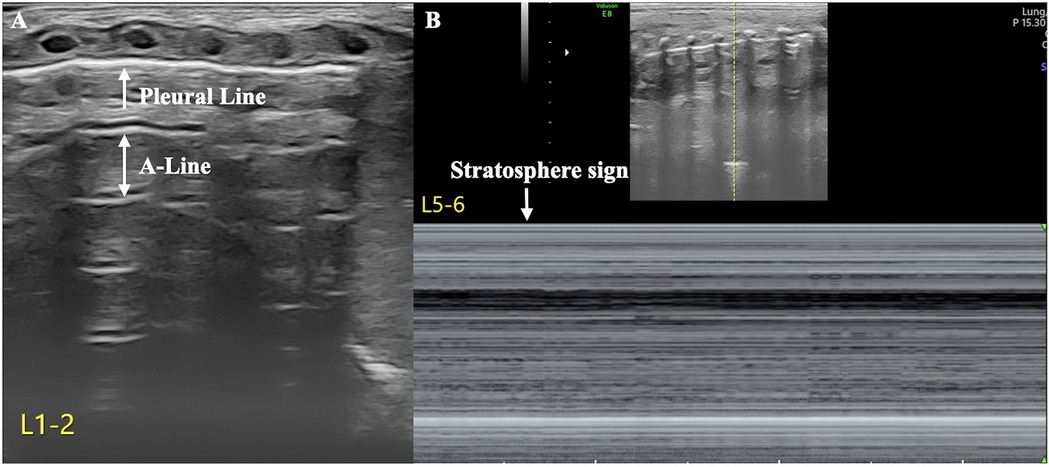

The patient's condition was relatively stable on the first and second days after birth, with noninvasive respiratory support maintaining stable vital signs. However, her respiratory distress suddenly worsened on the third day after birth, and the oxygen concentration required invasive respiratory support to maintain normal blood oxygen saturation without any obvious triggers. LUS reexamination revealed clear pleural lines and A-lines on B-mode ultrasound of the left anterior chest, axilla, and back. The stratosphere sign appeared on M-mode ultrasound. Real-time ultrasound revealed the disappearance of lung sliding. According to the diagnostic and grading criteria of PTX, this child meets the diagnostic criteria for severe PTX in the left thoracic cavity (9–11) (Figure 2, Supplementary Video S1). Moreover, ultrasound signs indicating a moderate degree of PTX were also observed in the anterior chest and the upper axillary region of her right thoracic cavity (9–11). In the lower field of the right axilla, an anechoic dark area was observed, and alternating visibility of the lung sliding was observed between the upper and lower fields on real-time ultrasound. Under M-mode ultrasound, these areas presented as alternating characteristics between the beach sign and the stratosphere sign, similar to the lung point (11, 12), confirming a small amount of pleural effusion combined with moderate pneumothorax, specifically hydropneumothorax (Figure 3, Supplementary Video S2).

Figure 2. Severe pneumothorax in the left thoracic cavity. LUS revealed clear pleural lines and A-lines in the anterior chest, axilla, and posterior chest of the left lung on B-mode ultrasound. M-mode ultrasound revealed the stratosphere sign, and real-time ultrasound revealed disappearance of lung sliding (Supplementary Video S1), suggesting a large amount of pneumothorax in the left thoracic cavity (A: B-mode ultrasound, B: M-mode ultrasound).